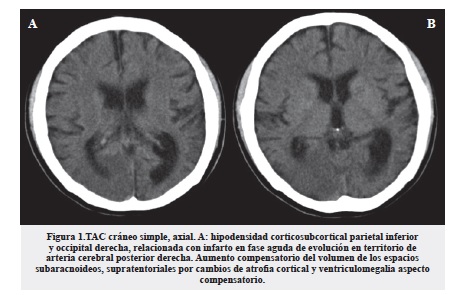

En la TAC cerebral simple como principal hallazgo encontramos una hipodensidad cortico - subcortical parietal inferior y occipital derecha, relacionada con infarto en fase aguda de evolución en territorio de arteria cerebral posterior derecha. Al igual que aumento compensatorio del volumen de los espacios subaracnoideos supratentoriales por cambios de atrofia cortical y ventriculomegalia compensatoria a la pérdida de volumen parenquimatoso (figura 1).

Los hallazgos por tomografía computarizada son inespecíficos, encontrando áreas de infarto predominantemente parieto-occipitales, calcificaciones o infartos en los núcleos de la base y atrofia cerebral desproporcionada para la edad6.